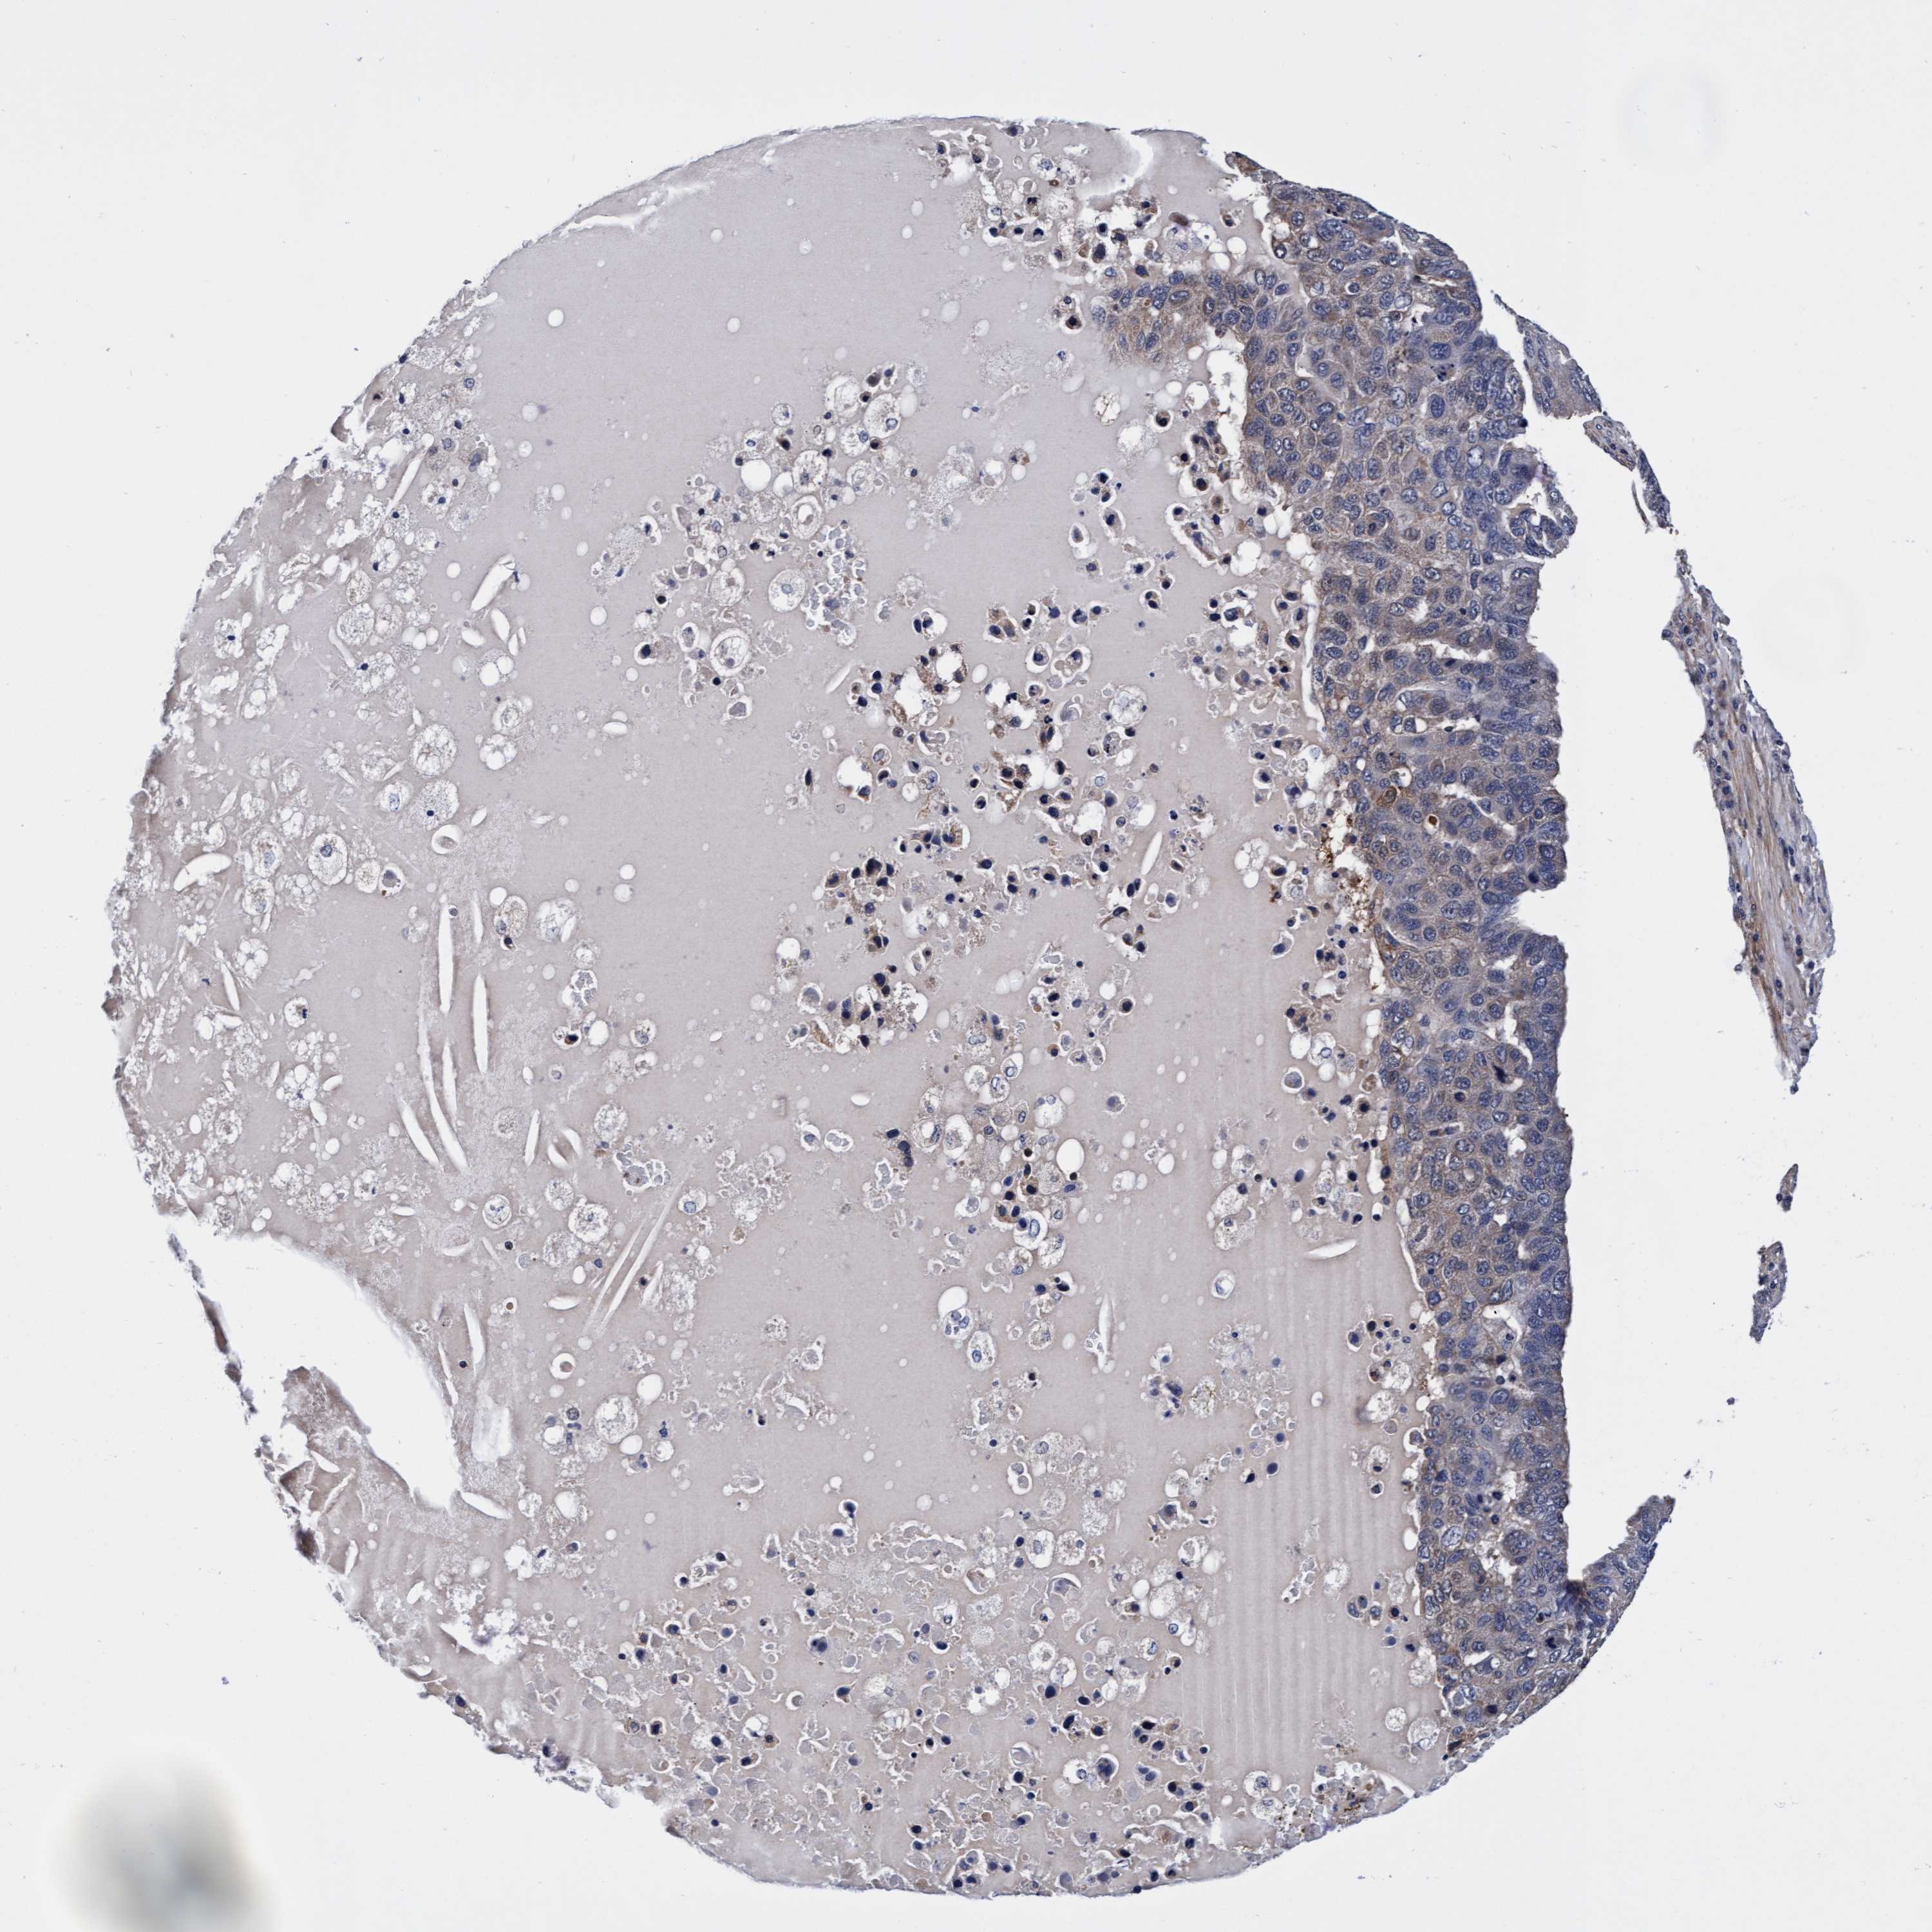

PANCREATIC CANCER - Protein expressioni

A mouse-over function shows sample information and annotation data. Click on an image to view it in a full screen mode. Samples can be filtered based on level of antibody staining by selecting one or several of the following categories: high, medium, low and not detected. The assay and annotation is described here.

Note that samples used for immunohistochemistry by the Human Protein Atlas do not correspond to samples in the TCGA dataset.

Antibody stainingi

Antibody staining in the annotated cell types in the current human tissue is reported as not detected, low, medium, or high, based on conventional immunohistochemistry profiling in selected tissues. This score is based on the combination of the staining intensity and fraction of stained cells.

Each image is clickable and will lead to virtual microscopy that enables deeper exploration of all samples and also displays staining intensity scores, fraction scores and subcellular localization as well as patient and tissue information for each sample.

Antibody HPA021633

Antibody HPA023249

Antibody HPA026561

Antibody CAB002501

Staining

High

Medium

Low

Not detected

Intensity

Strong

Moderate

Weak

Negative

Quantity

>75%

75%-25%

<25%

None

Location

Nuclear

Cytoplasmic/membranous

Cytoplasmic/membranous,nuclear

Adenocarcinoma, NOS

Adenocarcinoma, metastatic, NOS